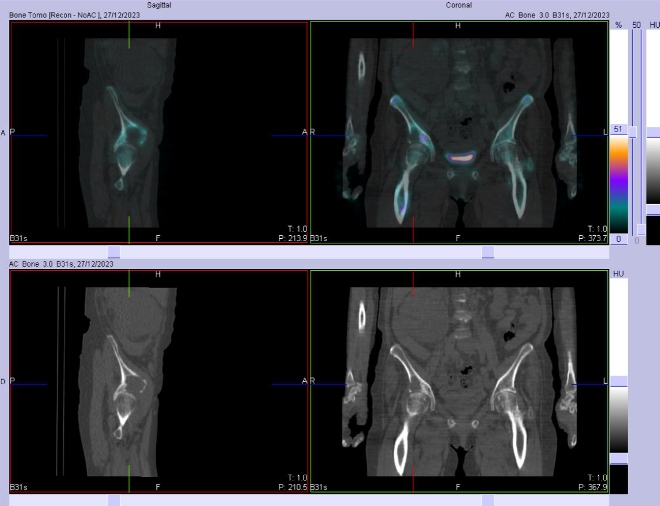

/ Obr. č. 8-10: Fúze obrazů SPECT a CT bederní páteře, pánve, kyčelních kloubů, proximální části stehenních kostí.

Patologické ložisko vyšší osteoblastické aktivity v proximální části diafýzy pravé stehenní kosti. Osteolytická léze v kosti kyčelní vpravo těsně nad pravým kyčelním kloubem zasahující zčásti i do acetabula, na jejím mediálním okraji je vyšší osteoblastická aktivita.

Nález odpovídá metastatickému postižení skeletu (jak osteolytická, tak osteoblastická metastáza). Degenerativní změny páteře.